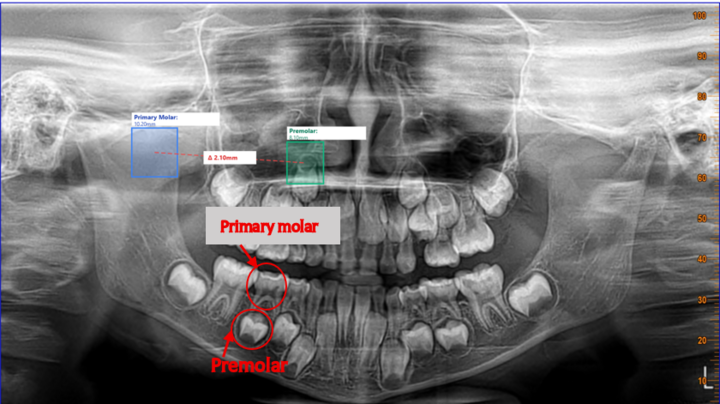

Visualizing Predictions

The model saves annotated images showing:

- 🟢 Green bounding box: Detected tooth region

- 📊 Confidence score: How certain the model is

- 🔖 Class label: "tooth"